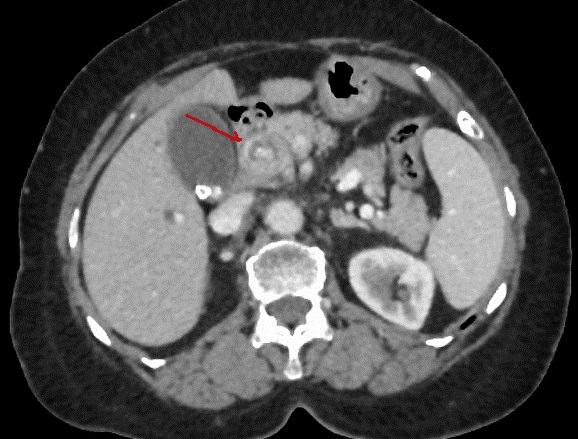

Image radiologique TDM +

contrast intra-veineuse en coupe axiale . Aspect de

cible en vue tres nette sur ce coupe ( fleche

rouge ) . Une contour de faible densite englobe une

noyaux hyperdensite . . |